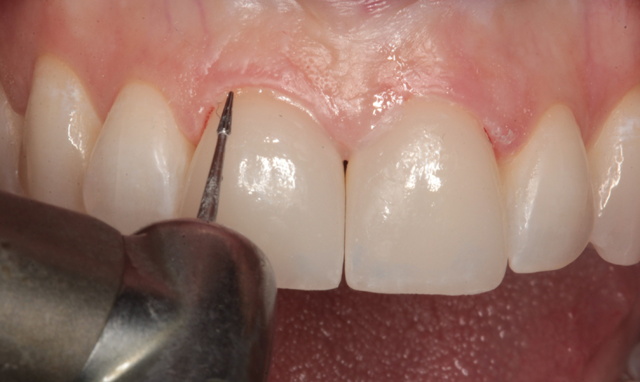

A small carbide finishing bur was used to remove remaining excess resin at the margins (Fig. 24). A number 12 surgical blade was used to remove some excess resin at the interproximal margins (Fig. 25). An Enhance Cup (Dentsply/Sirona) was used to smooth and polish margins and remove excess resin on the ceramic surfaces (Fig. 26).

Fig. 23 Fig. 24 Fig. 25